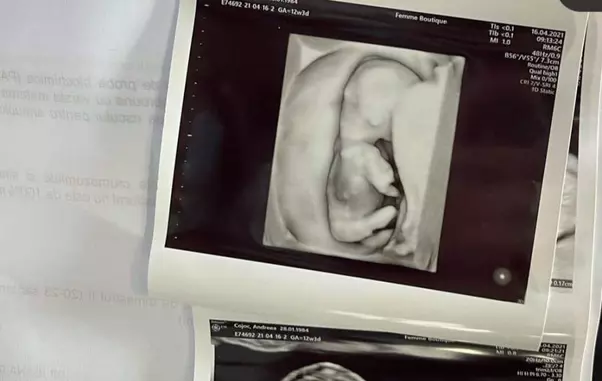

„A venit momentul să împărtășesc cu voi cea de a doua MINUNE de la Dumnezeu👶🏻. #13saptamani #3luni. Așa bucurie este în inima mea și mă bucur că am această șansă să îmi înmulțesc iubirea, răbdarea și credința.

Vom avea doi copii minunați și să ne dea Dumnezeu măcar înca pe atâția' , a scris Andreea Popescu pe pagina sa de Instagram, unde a postat câteva fotografii cu burtica și ecografia bebelușului.

„Acum suntem trei! Vreau să spun tuturor cât bine mi-a făcut Dumnezeu, cât de mult ne iubeşte. La morfologia de trei luni, mi-am văzut bebeluşul «dansând» în burtica mea, poate că seamănă cu tată-su, cum țopăia în sus şi în jos, cum îşi ducea mănuţa la gură, cum îşi întindea picioruşele şi bineînţeles inimioara care bătea repede, atunci nu am mai putut şi am început să plâng pentru că simţeam cum inima mea s-a umplut de fericire, o fericire pe care numai o mamă o simte.